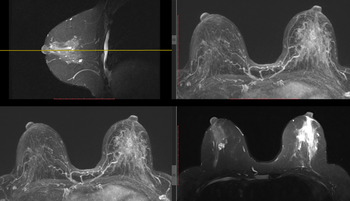

Disposant de toutes les modalités d'examen (Imagerie par Résonnance Magnétique (IRM), scanner, artériographie diagnostique et interventionnelle, échographie, mammographie, radiologie générale) et fort d'une équipe de 30 radiologues et 4 médecins spécialistes en formation, le Service d'Imagerie médicale de la Citadelle exerce son activité sur 4 sites (Citadelle, Herstal, Laveu et Valdor).